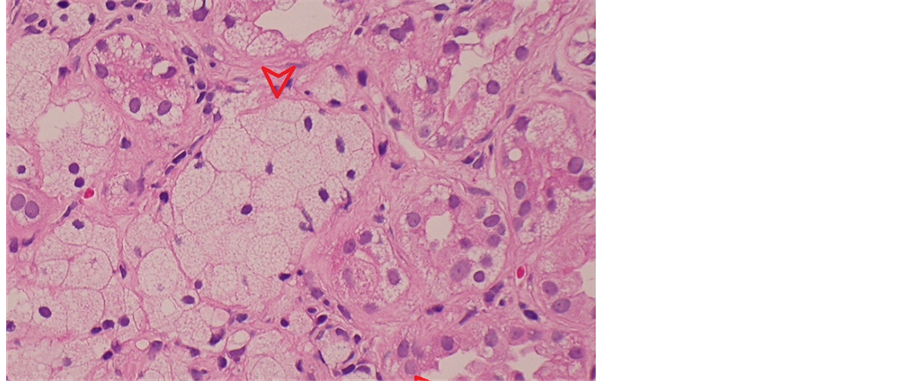

A 12-year-old girl presented with puffy face, bilateral lower-leg edema and frothy urine in recent two months. Biochemical studies showed nephrotic range proteinuria, hematuria > 30 erythrocytes per high-power field, lipiduria, serum cholesterol 10.1 mmol/l, albumin 16 g/l, and creatinine 30.5 mmol/l. Her blood pressure was 108/70 mmHg, and renin-angiotensin system blockers were not used. A kidney biopsy was performed for her nephrotic-nephritic syndrome with unclear etiology. Light microscopic examination with hematoxylin and eosin stain revealed rigidity and moderate thickening of the glomerular basement membrane (GBM), and segmental glomerular sclerosis. Accumulating an excessive amount of neutral fats in renal tubular cells led to extremely foamy appearance and luminal obliteration (Figure 1). Such fatty change is followed by necrosis of injured cells and detachement from the basement membranes compounding luminal obliteration. Electron microscopy depicted irregular distribution of GBM with basket-weave appearance (thinning, thickening, splitting and lamination of lamina densa) and diffuse effacement of podocyte foot processes (Figure 2). Myriad intracellular lipid droplets were noted within tubulointerstitial lipid-laden foamy macrophages (Figure 3).

Figure 1. Light microscopy depicted accumulating excessive lipids in renal tubular cells led to extremely foamy appearance and luminal obliteration (arrow). Such fatty change is followed by necrosis of injured cells and detachement from the basement membranes (arrow) compounding luminal obliteration.